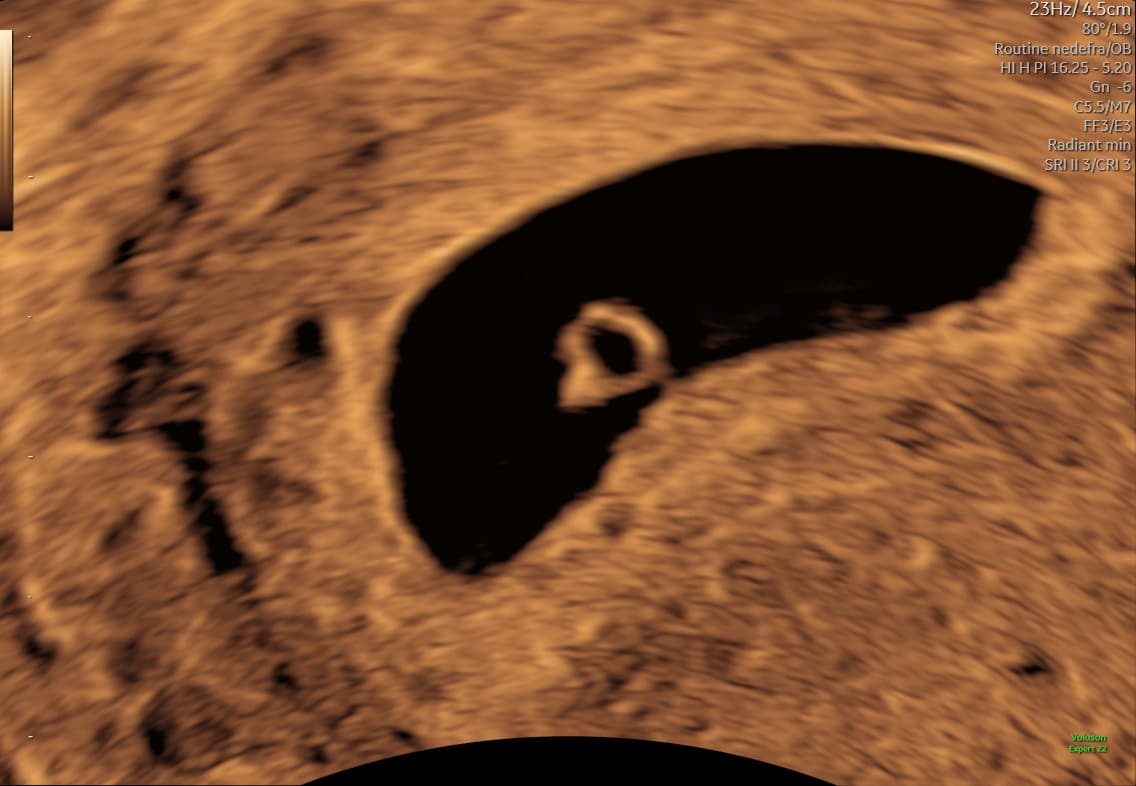

Ultralydsscanning uge 7 hjerteblink

Ultralydsscanning uge 8 lille foster i livmoderen

Eksempel på ultralyd i uge 7–8. Hjerteblink kan ofte ses, men synligheden varierer.

I denne periode kan bevægelse ofte ses tydeligere på video end på stillbilleder.

Kort ultralydssekvens fra uge 7, hvor hjerteaktivitet og tidlig bevægelse kan ses